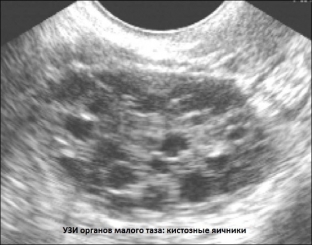

The diagnostic process of post-hysterectomy syndrome is based on a laboratory study of the hormonal background of a woman, as well as on an ultrasound examination of the pelvic organs. With posthysterectomy syndrome, the level of estradiol in the blood of women decreases to values ​​characteristic of the postmenopausal period. Characteristic is also an increase in the levels of follicle-stimulating and luteinizing hormones, which reflect the persistent extinction of ovarian function. Ultrasound examination demonstrates characteristic changes in the ovaries after hysterectomy. In the early postoperative period, the volume of the ovaries increases by almost one and a half times as a result of their cystic transformation, Dopplerography indicates a decrease in blood flow and the occurrence of venous congestion in the small pelvis.